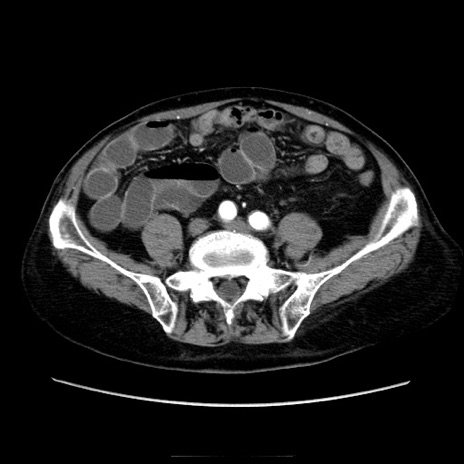

症例21(横断像)

【症例】70歳代男性

【主訴】腹痛

【現病歴】肝硬変・肝細胞癌にてかかりつけの方。約9時間前に食後より腹痛出現。症状が徐々に増悪し、嘔吐出現したため来院。

【既往歴】肝硬変、肝細胞癌(RFA、TACE後)

【身体所見】意識清明、表情苦悶様、BT 36℃、BP 129/78mmHg、P 88bpm、SpO2 97%(RA)、右上腹部から心窩部にかけて圧痛あり、反跳痛なし、筋性防御あり。

【データ】WBC 5800、CRP 0.16